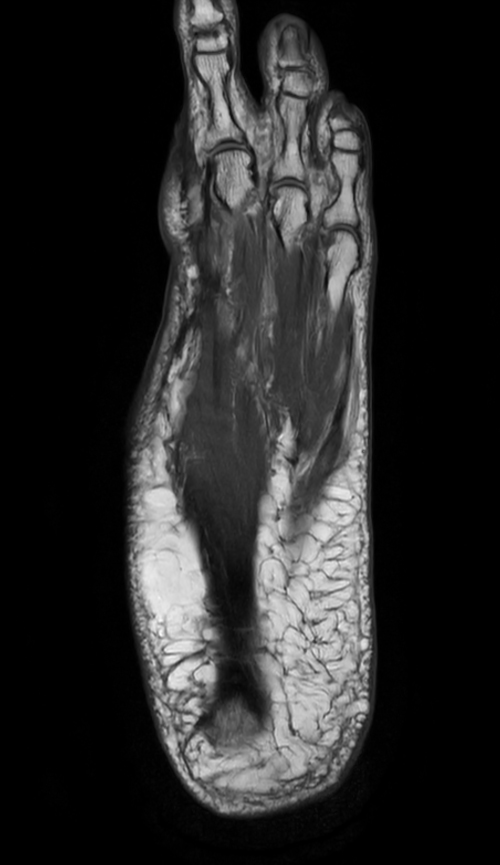

Ankle/Foot imaging post-amputation

Patient with partial amputation of the foot

Coronal PDw mDIXON XD TSE (Water only)

-

Coronal PDw mDIXON XD TSE (In Phase)

Coronal PDw mDIXON XD TSE (Partial FatSat)